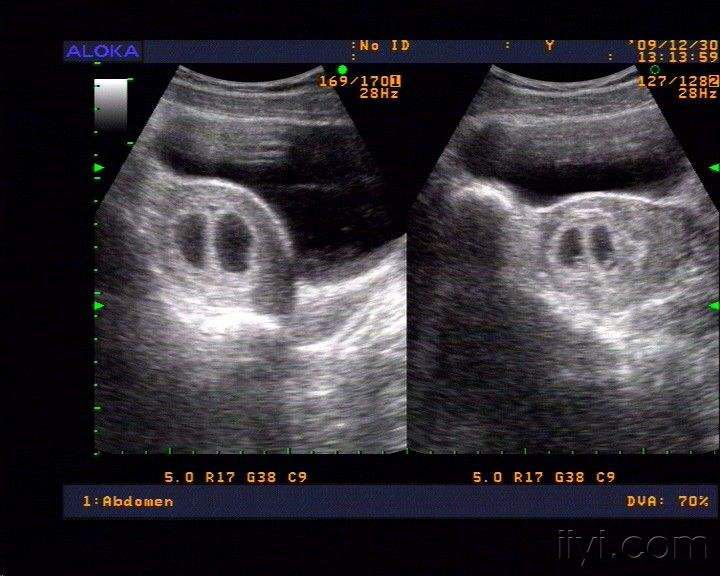

宫内早孕双胎妊娠

停经50天余,自测尿hcg试纸阳性

查彩超示宫内早孕,双绒双羊

诊断宫内早孕